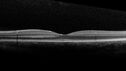

8 Year old with no symptoms and no family history of vision problems

Coats' Disease - 8-year-old boy - Asymptomatic303 viewsNormal vision - Lesion picked up on examination00000